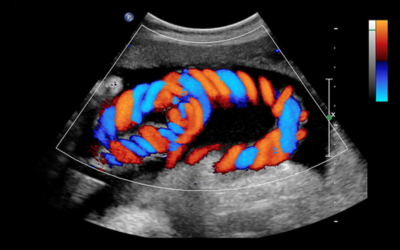

Echocardiography (echo)

The cornerstone of diagnosis, this non‑invasive ultrasound test precisely maps the size, location, and hemodynamics of the defect.

Color Doppler study

Measures how blood flows through the opening and checks heart function.